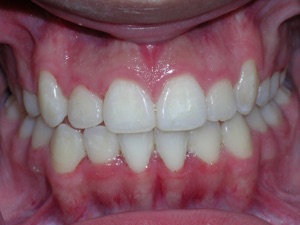

Here’s an example from a young boy who had very significant crowding. One can see that the canines on top and bottom are blocked out. There was also an overbite. The combination made the case challenging. Watch.